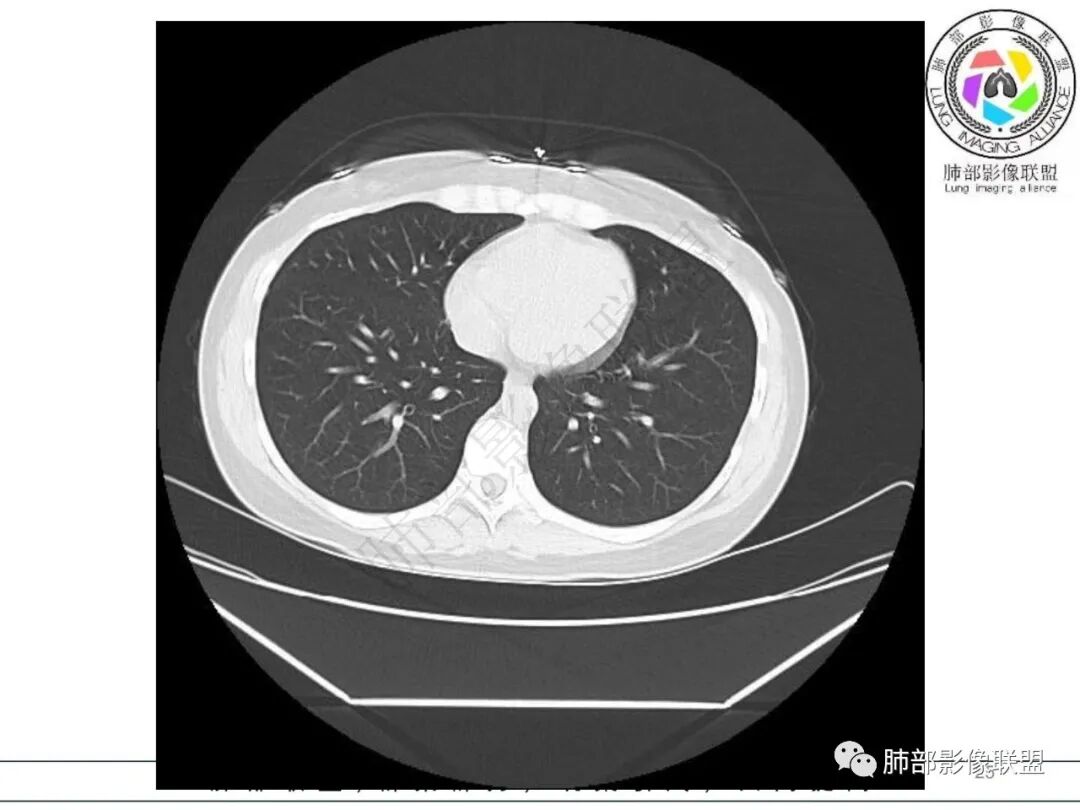

2.影像特征:右肺下叶局限性实变影伴晕征,边界不清,内部支气管尚通畅,实变区密实区边缘稍膨隆。符合炎性病灶特征。

右肺下叶局限性实变影伴晕征。

年轻女性,发热,白细胞略低,超敏CRP高,右肺下叶团片影,边缘毛糙,周围见磨玻璃晕,其内含气细支气管,考虑炎性肉芽肿,侵袭性曲霉菌感染?鉴别淋巴瘤

女,34,畏寒、发热3天,伴纳差、恶心、呕吐。血像不高,ESR、CRP增高。胸部CT:右肺下叶局限斑片影,边缘模糊,内可见支气管穿行,个别层面融冰?肺动脉貌似增粗,考虑不典型病原体感染?肺梗?鉴别淋巴瘤等。